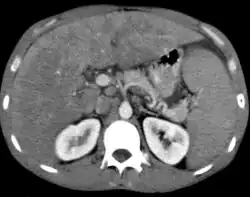

-

Non-Hodgkin lymphoma - splenic involvement -